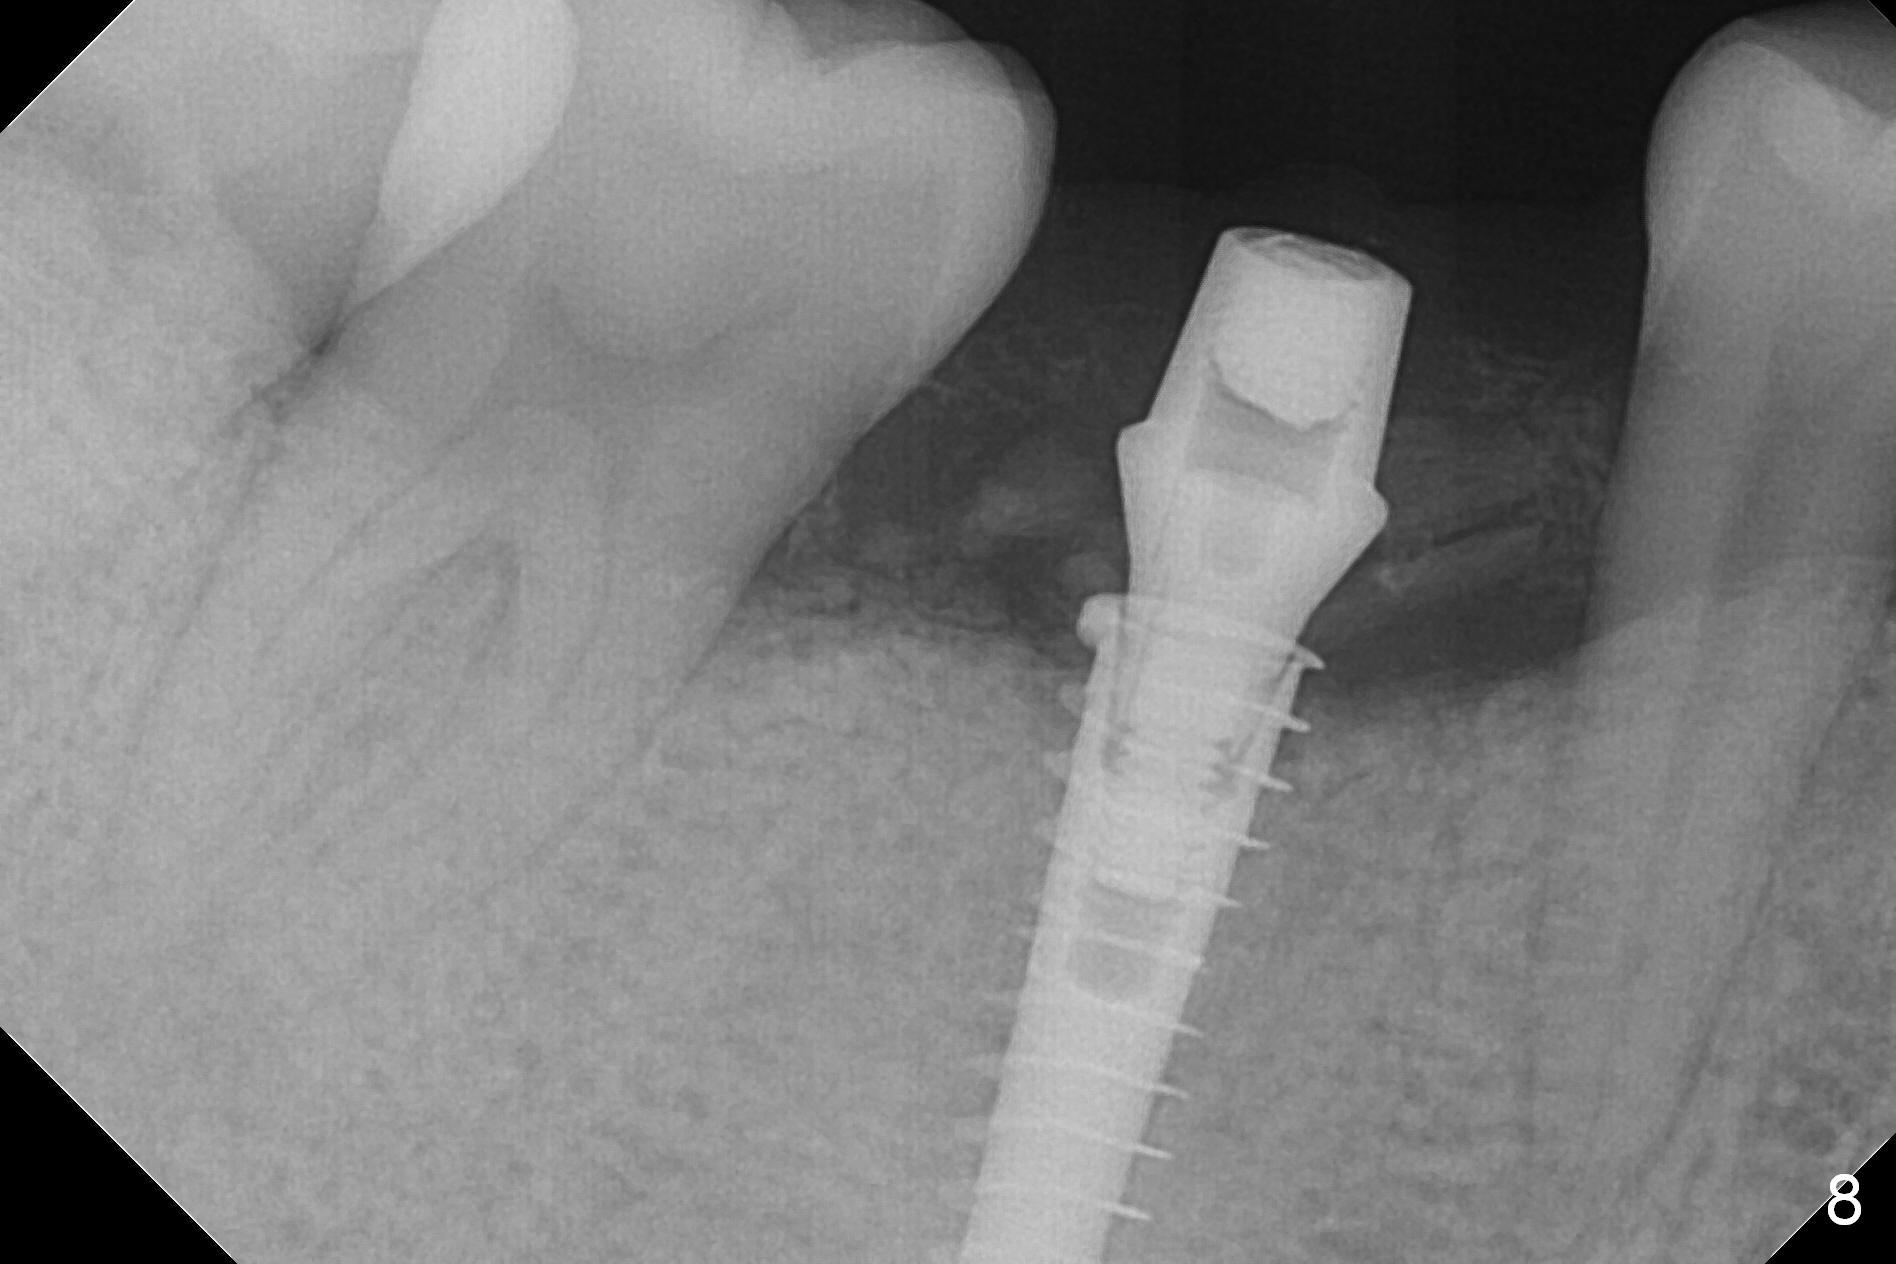

The patient returns 5.5 months postop for final restoration. The implant appears to have osteointegrated (Fig.8). When the locked in provisional is removed, the gingiva bleeds (Fig.9). She will return in 2 weeks. The abutment remains incompletely seated nearly 2 years post cementation (Fig.10).